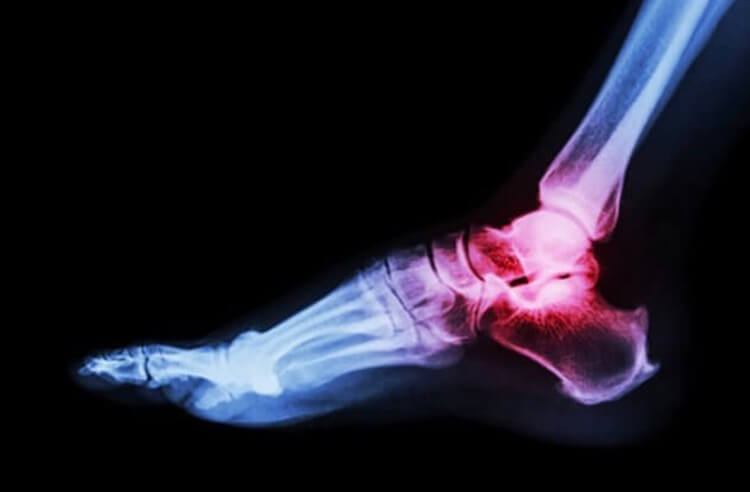

Несокрушимые кости

Некоторые люди обладают действительно крепкими костями.

Сломанная кость — удивительно простой способ поломать вам целый день (и следующие несколько месяцев). Хотя кости — это самые прочные вещества в человеческом теле, они, безусловно, уязвимы. Если только у вас нет редкой мутации гена LRP5.

LRP5 отвечает за плотность костей. Ученые уже знают, что мутации в этом гене могут привести к снижению плотности костной ткани, или остеопорозу. Тем не менее в последнее время они также выяснили, что мутация гена может привести и к обратному эффекту. Одна семья в Коннектикуте, как оказалось, имеет мутации LRP5, которые дают их костям такую плотность, что те практически неразрушимы. Никто из них никогда не ломал кость. Увеличенная сила костей, в особенности позвоночника, черепа и таза, дает членам этой семьи самые прочные скелеты на Земле.

Ученые считают, что эта мутация вызывает слишком много сигналов костного роста, которые приводят к уплотнению костей и, соответственно, сверхсиле. Хотелось бы надеяться, что в один прекрасный день контролируемую форму мутантного гена можно будет использовать, чтобы положить конец мутациям костей.